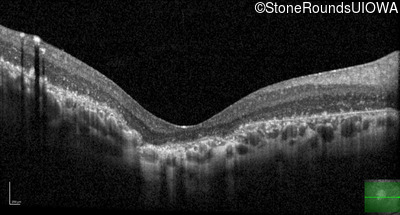

Optical Coherence Tomography - Right - 20/1000 sc

Exemplar / OCT Stack